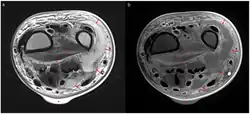

Axial T2 weighted MRI (a) and contrast-enhanced MRI (b) of left wrist showing necrotizing fasciitis. There is diffuse hyperintensity with irregular enhancement of the deep fascia (asterisks). The arrows indicate a lobulating abscess, and the triangle a skin bulla.

Magnetic resonance imaging (MRI) is considered superior to computed tomography (CT) in the visualization of soft tissues and is able to detect about 93% of NF cases.[15] It is especially useful in finding fluid in the deep fascia, which can distinguish between NF and cellulitis.[15] When fluid collects in the deep fascia, or thickening or enhancement with contrast, necrotizing fasciitis should be strongly suspected. However, MRI is much slower than CT and not as widely available.[15] There may also be limitations on its use in patients with kidney problems.[15]